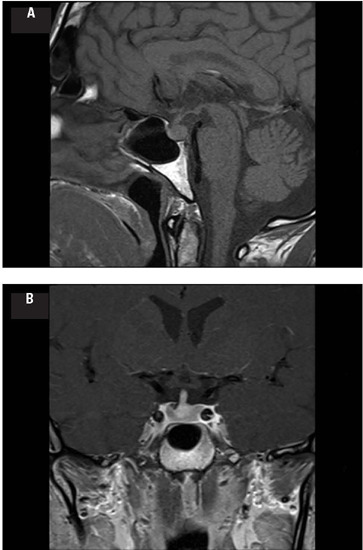

长冠状病毒病的定义是在COVID-19之后出现的体征、症状和条件,可能影响多个器官和系统。精氨酸-抗利尿素缺乏症;中心性尿崩症是COVID-19和SARS-CoV-2免疫接种后非常罕见的并发症。从PubMed检索截至2024年2月发表的关于AVP-D和long COVID的病例报告、原始研究和评论。一名47岁男性在轻度COVID-19发作8周后出现多饮、多尿、记忆丧失和精神雾。他过去的个人和家族病史没有什么特别之处。生化评价与低尿渗透压和24小时尿量10,350 mL有关。垂体基底前叶评价正常。由于出现高钠血症、高血清渗透压和低尿渗透压,开始进行水剥夺试验,2小时后中断。鼻内降压素20 μg后,尿渗透压显著升高。垂体造影增强MRI提示垂体神经炎。进一步的生化、遗传和影像学检查排除继发性AVP-D原因。患者随后开始口服去氨加压素,反应迅速。在20个月的随访后,他的AVP-D控制良好。尽管尚无法对SARS-CoV-2大泡神经垂体炎的分子和组织学证实进行研究,但其强烈的时间关系和缺乏替代诊断使得AVP-D在无数长期COVID表现中包含似乎是合理的。为了更好地了解这种非常罕见的内分泌疾病的流行病学、病理生理学和临床过程,有必要对COVID-19康复患者进行进一步研究。

Long COVID is defined by the occurrence of signs, symptoms, and conditions that develop after COVID-19 and may affect several organs and systems. Arginine-vasopressin deficiency (AVP-D; central diabetes insipidus) is a very rare complication of COVID-19 and SARS-CoV-2 immunization. Case reports, original studies, and reviews on AVP-D and long COVID published until February 2024 were retrieved from PubMed. A 47-year-old man presented with polydipsia, polyuria, memory loss, and mental fog 8 weeks after an episode of mild COVID-19. His past personal and family medical history were unremarkable. Biochemical evaluation was relevant for low urine osmolality and a 24-hour urine volume of 10,350 mL. Basal anterior pituitary evaluation was normal. A water deprivation test was started and interrupted after 2 hours due to the development of hypernatremia, high serum osmolality, and low urine osmolality. Urine osmolality significantly increased after intranasal desmopressin 20 μg. Contrast-enhanced pituitary MRI was suggestive of infundibulo-neurohypophysitis. Further biochemical, genetic, and imaging tests excluded secondary AVP-D causes.The patient was subsequently started on oral desmopressin, showing prompt response. After a follow-up of 20 months, he remained well-controlled with isolated AVP-D. Although molecular and histologic confirmation of SARS-CoV-2 infundibulo-neurohypophysitis could not be investigated, a strong temporal relationship and the absence of an alternative diagnosis rendered plausible the inclusion of AVP-D in the myriad of long COVID manifestations. Further studies with patients recovered from COVID-19 are necessary for a better understanding of the epidemiology, pathophysiology, and clinical course of this very rare endocrine condition.